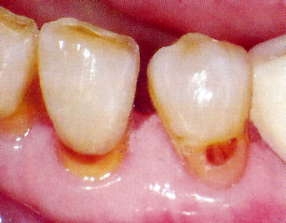

○光CR充填

光CR(白いつめる材料)を使用した、むし歯治療に取り組んでいます。健康保険適用。

右:歯の根元の茶色の部分がむし歯です。

左:患者様の歯の色に合わせたCRで充填しました。